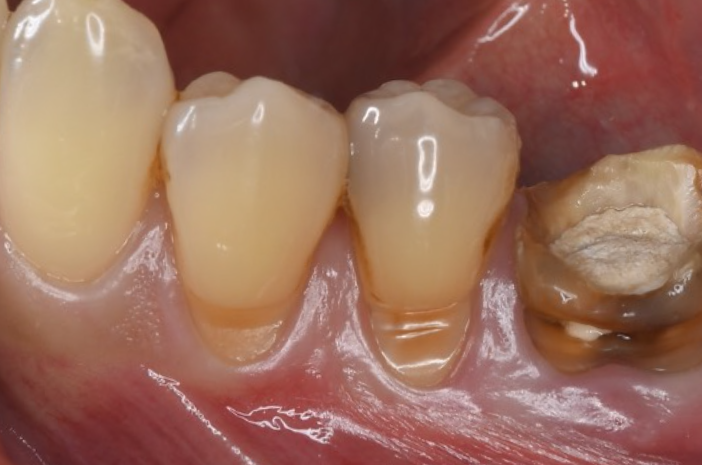

症例3

| 項目 | 詳細 |

|---|---|

| 患者様データ | 50代 男性 |

| 来院時の主訴 | 「左下の歯が歯磨きでしみる。」 |

| 医院の診断 | 歯肉退縮・歯周病(根分岐部病変) |

| 通院期間 | 1年 |

| 来院回数 | 12回 |

| 治療費 | 総額:630,000円(税抜) 【内訳】 歯周組織再生療法220,000円 歯肉結合組織移植術170,000円 セラミック治療120,000円×2 |

| リスクと副作用 | 定期的なメンテナンスが必要、術後若干の腫れと痛み |

| ここがこだわりのポイント!☝ | 歯周病と歯茎下がりを同時に解決しました。歯肉の厚みが増したことで、歯磨きがしやすくなり、歯がしみる症状も改善しました。 |